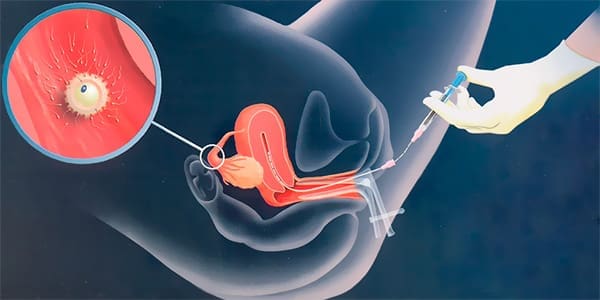

¿Por qué elegir una clínica especializada en alta complejidad reproductiva?

La búsqueda de un embarazo puede llegar a ser un proyecto largo y lleno de incertidumbre, sobre todo cuando el resultado no llega en el momento esperado. Muchas mujeres y […]